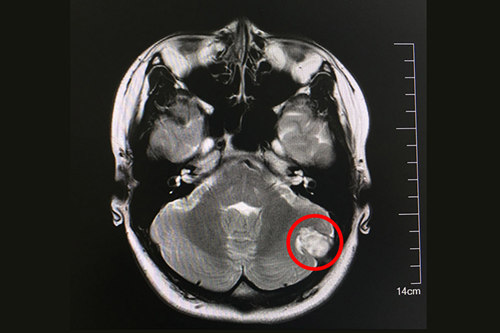

术前核磁显示:左侧后颅窝实性脑外占位病变,与左枕骨宽基相连